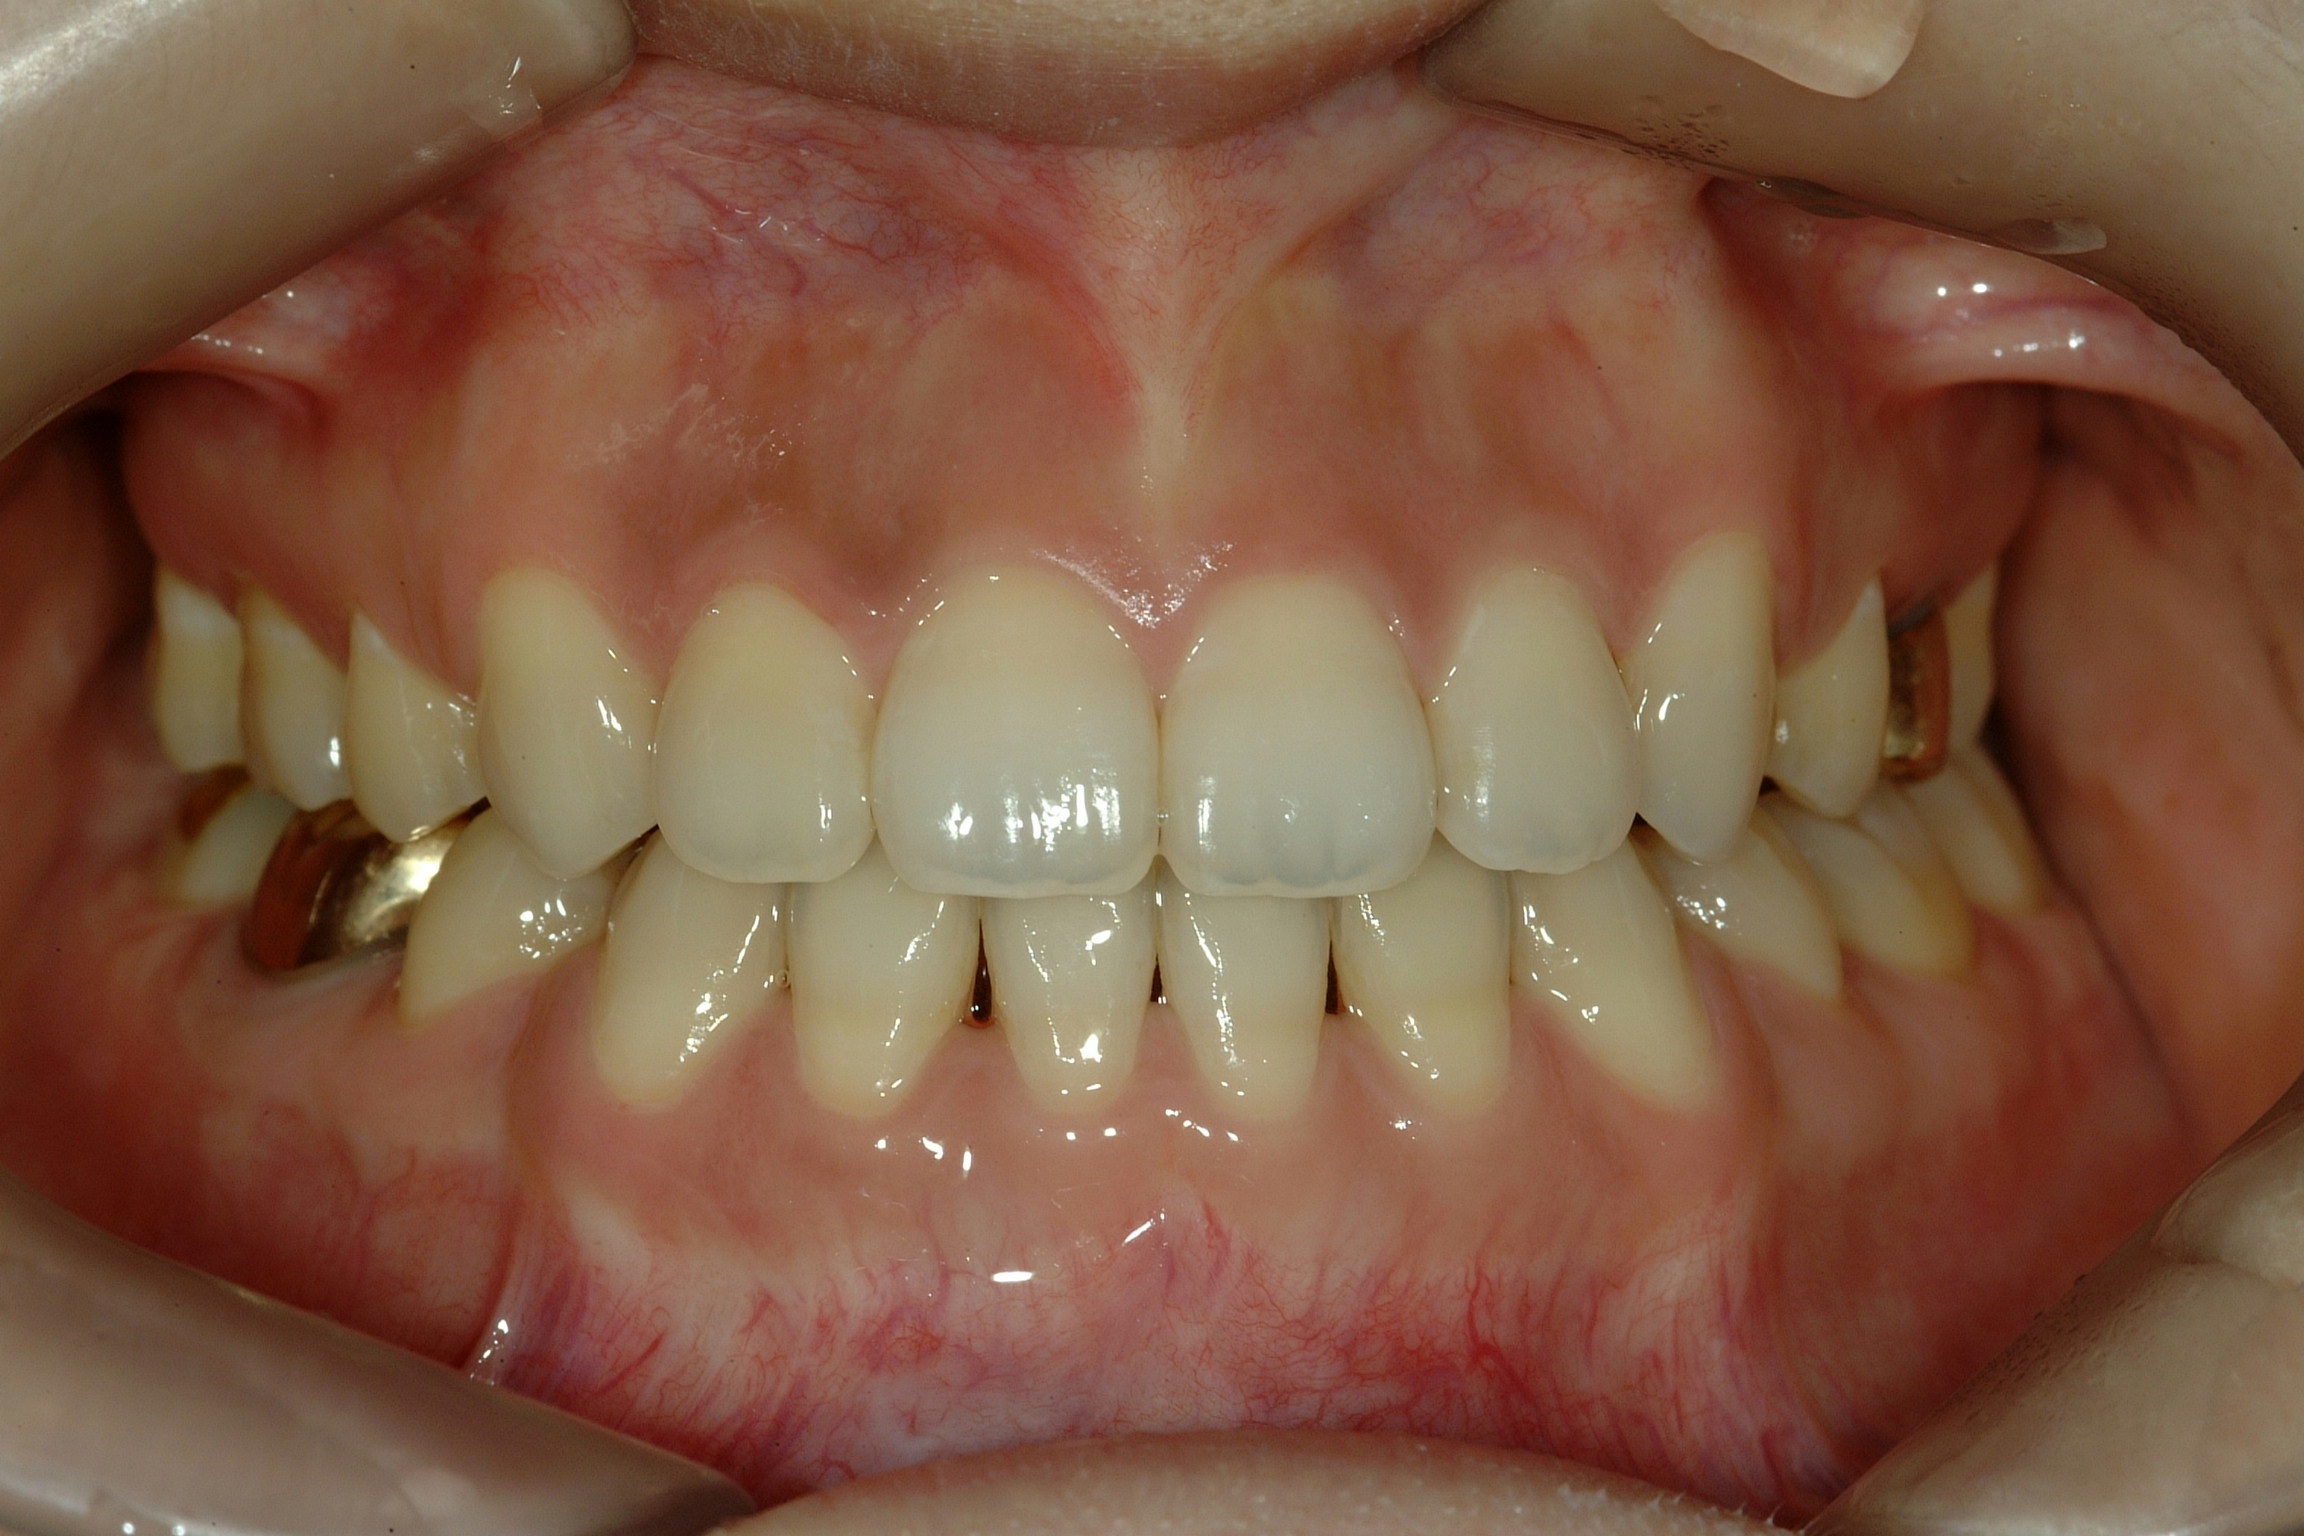

치료 후 사진입니다.